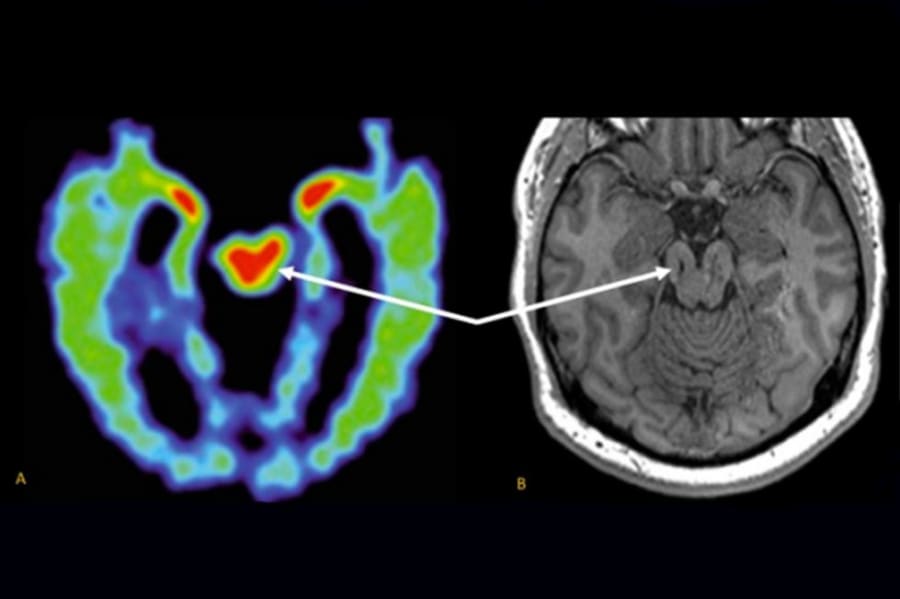

Resonancia magnética de una lesión cerebral. UCLA Health. Comparación entre una tomografía por emisión de positrones (PET) de un jugador de la NFL, que revela una acumulación anómala de proteínas característica de la encefalopatía traumática crónica (izquierda), y una resonancia magnética que muestra un mesencéfalo anormalmente pequeño en un antiguo jugador de fútbol americano de instituto. Ambos pacientes presentan sospecha de patología de ETC en la región del mesencéfalo (flechas).

Resonancia magnética de una lesión cerebral. . Comparación entre una tomografía por emisión de positrones (PET) de un jugador de la NFL, que revela una acumulación anómala de proteínas característica de la encefalopatía traumática crónica (izquierda), y una resonancia magnética que muestra un mesencéfalo anormalmente pequeño en un antiguo jugador de fútbol americano de instituto. Ambos pacientes presentan sospecha de patología de ETC en la región del mesencéfalo (flechas).